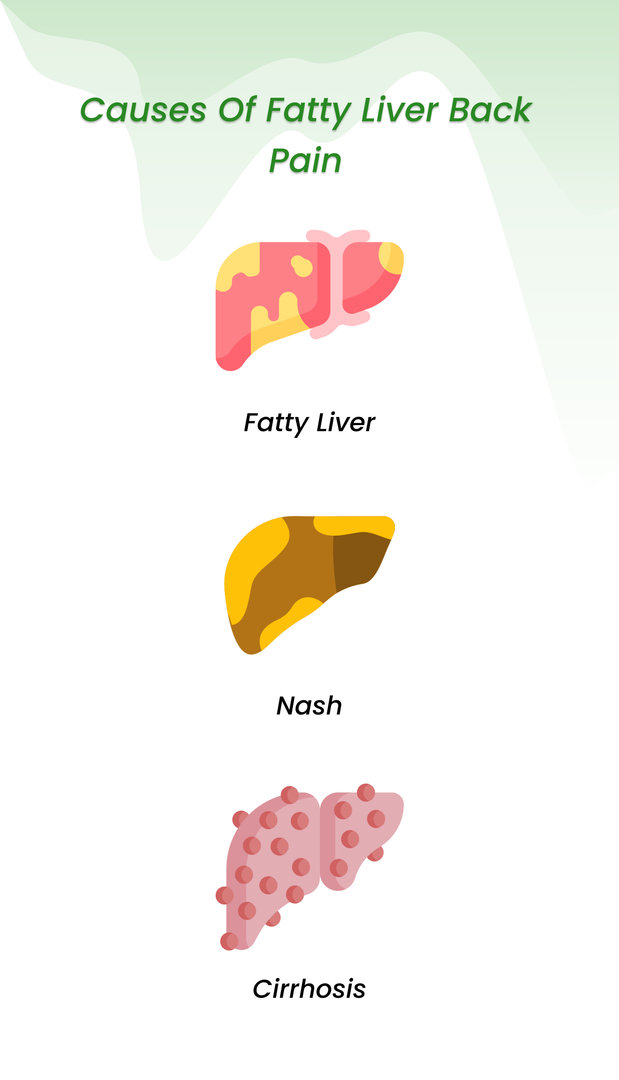

The Comprehensive Guide Of Fatty Liver Back Pain Strategies And